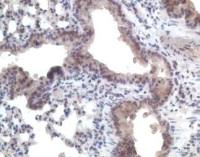

mGluR2/3 polyclonal antibody (1:250 dilution) was used on perfusion-fixed tissue from rat spinal cord.